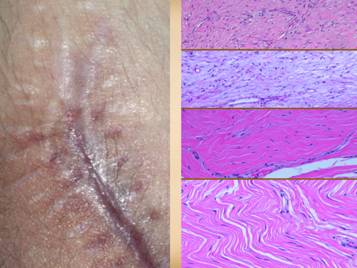

Left upper:  rheumatoid, ulceration over and into small joints.  Left center:  rheumatoid, ulceration along old scar.  Left lower:  scleroderma, livedo reticularis, ulceration along tendons (this ulcer is not under the metatarsal heads).  Left inner:  rheumatoid, ulceration along old scar and tendon.  Right inner upper:  rheumatoid, ulceration in unusual area along tendons (thigh, hamstrings).  Right inner lower:  lupus-mctd, atrophie blanche dermal scarring.  Right upper:  rheumatoid, wound failure of unlikely location (abdomen).  Right lower:  rheumatoid and hypercoagulable, wound failure of unlikely location (forearm), ulceration along muscle and tendon, necrosis around staples.

Left upper:  rheumatoid arthritis, with acute panniculitis and multifocal ulceration.  Note the inflammatory-lytic pattern of ulceration, skin dissolution without infarcted eschar.  Left middle:  rheumatoid, with multifocal inflammatory-lytic ulcers.  Left lower:  lupus or mixed ctd, with atrophie blanche, dermal scarring from repetitive episodes of connective inflammation.  Right upper:  lupus, with suppurative synovitis.  Right middle:  scleroderma-crst, with typical features of fingertip ulcers and necrosis, telangiectasias and sclerodactyly.  Right lower:  lupus, with atopic reaction to common dressing materials.